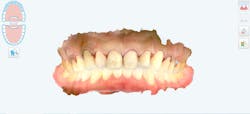

The new digital approach (figures 2–13) to an osseous crown lengthening procedure involves photographs, radiographs, intraoral scans, and CBCT data for a facially driven treatment plan. This approach starts with the end result in mind and ultimately requires fewer appointments for the patient. It also leads to more predictable esthetic results.

Once the patient accepts treatment and is on board for the crown lengthening as proposed, a surgical guide stent must be created and printed for approximation of the new crown margins. Using the smile creator Exocad, a digital mock-up of the final margins of the newly lengthened teeth is generated. The patient can be presented with the simulated smile and accept the look of the mock-up before digitally fabricating the surgical guide needed to achieve said results.

Utilizing a facially driven treatment plan, the facial photographs were merged with the CBCT scan to assess bone levels, and the central incisors were digitally planned to exhibit a new length of 11.5 mm, to enhance the patient’s long facial structure. The new width of the veneers could then be generated to be 85% of this measurement to achieve the golden proportion for optimal esthetics. Once the surgical guide is designed in Exocad to achieve these coronal margins, the guide design is exported to SprintRay to be printed with a snug fit for accurate coronal margination for the final restorations later on.